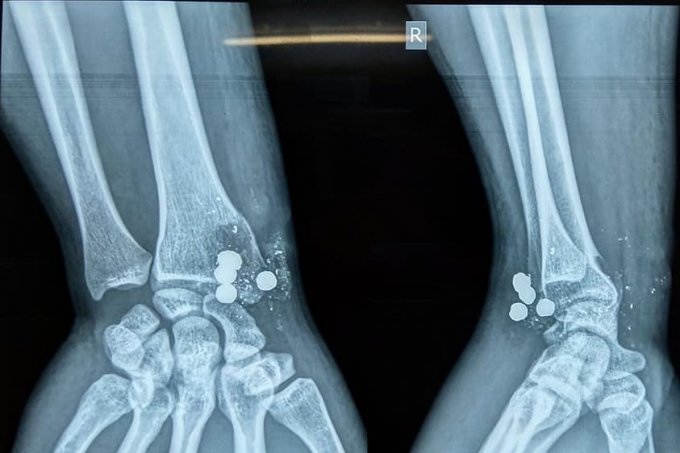

Hình ảnh chụp Xquang cho thấy nhiều mảnh đạn găm trong cổ tay nam bệnh nhân.

Trong cổ tay anh Th còn 4 mảnh đạn lớn bằng chì và nhiều mảnh kim loại nhỏ khác, 1 viên lớn đã xuyên từ trước ra sau.